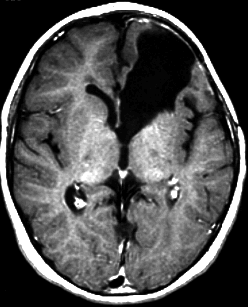

典型的な画像(未分化胎児性腫瘍の組織像を持つもの)

頭痛と嘔吐でみつかった年長児10歳のPNETです。脳外科の先生に上手に手術で全摘出していただいて,すぐに脳脊髄照射25.2グレイ14分割と局所追加照射30グレイ15分割の治療を受けました。その後に相談に来られたので,テモゾロマイド化学療法を24コース追加しました。

腫瘍は消失して元気に学校へ通えています。治療後IQは108あるのですが,右の前頭葉の上前頭回という所に発生したのが幸いであったかもしれません。この場所は確実に摘出できるからです。